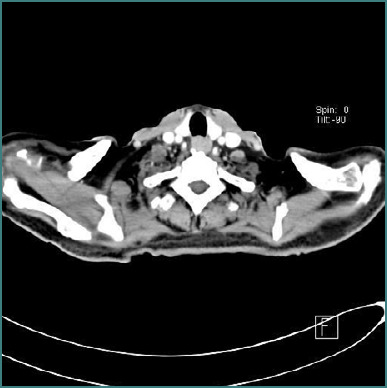

慢性炎症性脱髓鞘性多神经根病(CIDP)是一种获得性免疫介导的神经病变,其特征是进行性或复发缓解的近端和远端虚弱。淋巴瘤是与CIDP相关的多种血液恶性肿瘤之一。脾边缘区淋巴瘤(SMZL)是一种罕见的惰性b细胞非霍奇金淋巴瘤,典型表现为脾肿大和细胞减少。SMZL与CIDP同时发生极为罕见;因此,诊断提出了一个独特的挑战,无论是诊断和治疗。我们报告一位65岁男性病患,表现为进行性近端无力、盗汗及脾肿大。检查显示全血细胞减少,影像学检查证实脾肿大。进一步的检查,如骨髓活检和脾脏组织病理学,分别表明骨髓和SMZL细胞减少。同时,根据临床表现,以及肌电图和神经传导检查,建立CIDP的诊断。对于CIDP,开始免疫抑制治疗;然而,由于其惰性性质,未对SMZL进行治疗。他在接受CIDP治疗后表现出部分神经系统改善。这强调了治疗这两种疾病的重要性。在本病例中提出了罕见的CIDP和SMZL的关联,强调了对神经和血液异常患者进行全面诊断的重要性。因此,对于此类患者的管理,及时识别和适当的治疗方法对于改善结果是必要的。

Chronic inflammatory demyelinating polyradiculopathy (CIDP) is an acquired immune-mediated neuropathy characterized by progressive or relapsing-remitting proximal and distal weakness. Lymphomas are among various hematological malignancies associated with CIDP. Splenic marginal zone lymphoma (SMZL) is a rare, indolent B-cell non-Hodgkin lymphoma that classically presents with splenomegaly and cytopenia. The co-occurrence of SMZL and CIDP is extremely rare; the diagnosis thus presents a unique challenge both diagnostically and therapeutically. We report a 65-year-old male patient with progressive proximal weakness, night sweats, and splenomegaly. Investigations revealed pancytopenia with imaging studies confirming the splenomegaly. Further investigations, such as a bone marrow biopsy and histopathology of the spleen, were indicative of a hypocellular marrow and SMZL, respectively. Simultaneously, a diagnosis of CIDP was established based on clinical findings, as well as electromyography and nerve conduction studies. For CIDP, immunosuppressive therapy was initiated; however, no treatment was administered for SMZL due to its indolent nature. He showed partial neurological improvement with the treatment given for CIDP. This underlines the importance of treating both diseases. The rare association of CIDP and SMZL is presented in this case, highlighting the importance of a comprehensive diagnostic workup in patients with neurological and hematological abnormalities. Therefore, for the management of such patients, timely identification and appropriate therapeutic approaches will be necessary for an improved outcome.